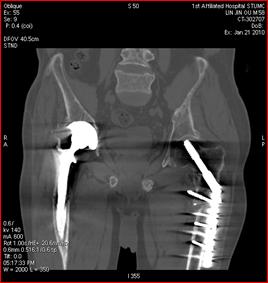

常規(guī)CT 寶石能譜CT

140keV能量成像可以除去金屬引起的偽影,更加清晰觀察術(shù)后情況